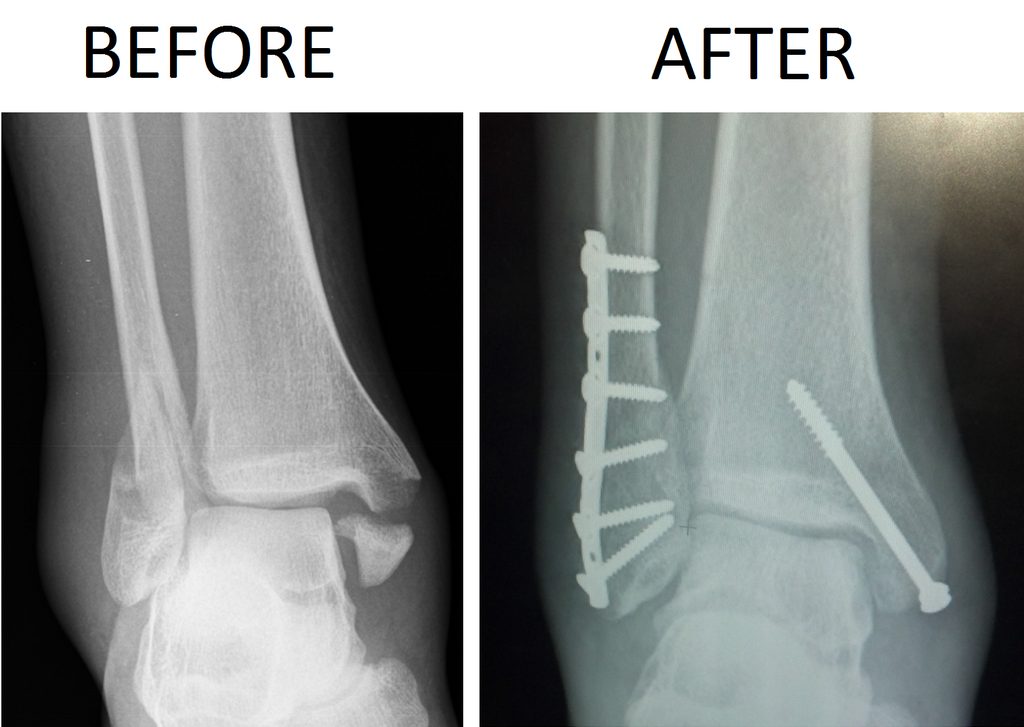

- Surgery is needed to “set” the bones after a bi or trimalleolar fracture occurs.

The treatment for a bi or trimalleolar fracture begins immediately. The ankle should be stabilized, and the person should be transported to the emergency room. Surgery is required to “fix” these fracture sites. It involves re-positioning the bones to their normal anatomical alignment and holding them in place with screws and plates. Following surgery the patient will be completely non-weight bearing for a period of 2-3 months. The repaired ankle will be incapable of bearing any weight for a long period of time and doing so could shift the placement of the repaired bones. Any misalignment of the bones could predispose the patient to an early onset of osteoarthritis in the joints of the ankle/foot complex.